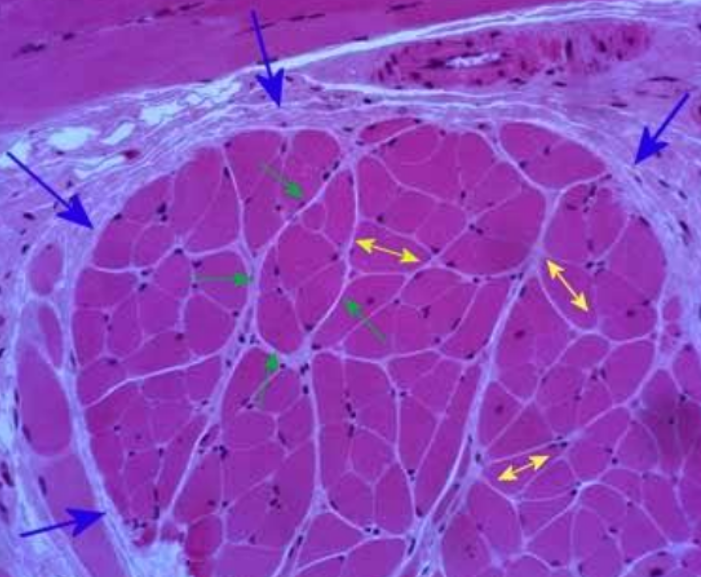

What cross section is this?

Skeletal muscle

What is the BLUE arrows pointing to?

epimysium

What is the YELLOW arrows pointing to?

endomysium

What is the GREEN arrows pointing to?

perimysium